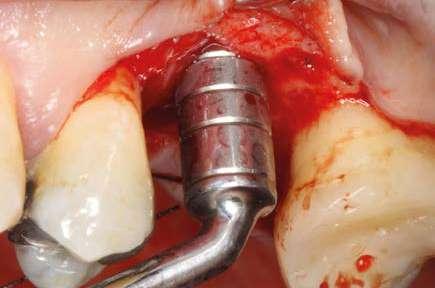

Figuras 5 y 6. Inicio de fresado de la cortical inferior del seno maxilar con la fresa de corte frontal.

Figuras 7 y 8. Despegamiento de la membrana para comenzar la elevación transcrestal.

Figuras 9 y 10. Inserción de membrana de fibrina como material de relleno en el neo-alveolo y colocación del implante.